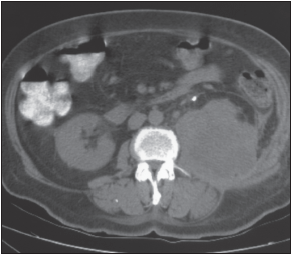

An ultrasonogram of the abdomen discloses a large hypodensity in the right lobe of the liver. The abdominal CT scan is shown here.

The abdominal CT scan shows a large, welldemarcated, hypodense lesion in the right lobe of the liver, consistent with an abscess. Features that strongly suggest pyogenic liver abscess, B, include high fever, progressive upper right quadrant pain, an enlarged liver, and a large hypoechoic lesion on ultrasonograms and CT scans.

The patient is initially treated with IV metronidazole, 200 mg every 8 hours. After aspiration, piperacillin with tazobactam, 1.5 g every 8 hours, is added. Percutaneous catheter drainage is established. After a week, the drainage fluid is less than 10 mL in 24 hours. A repeated abdominal CT scan reveals almost complete resolution of the abscess, and the drain is removed. The symptoms, including fever and pain, resolve within a week.